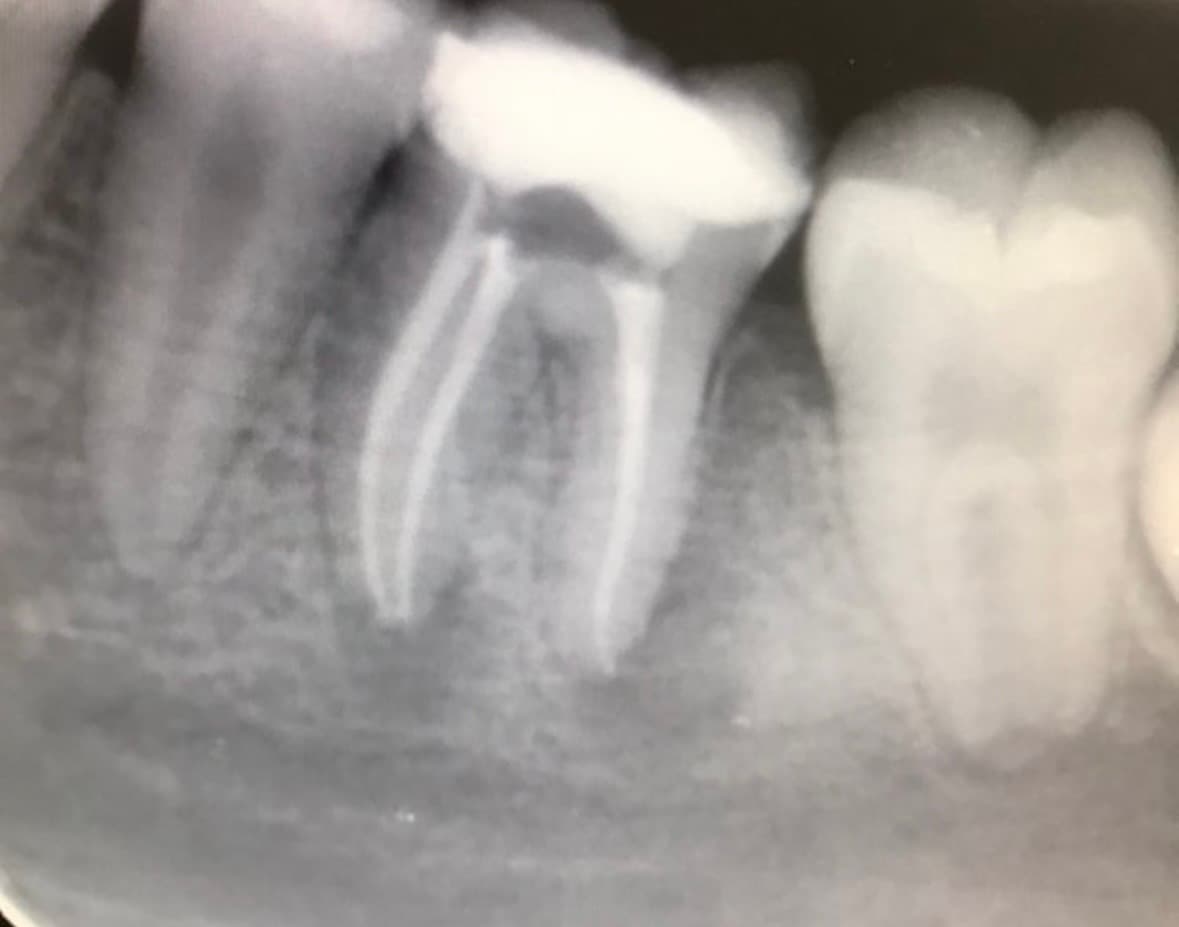

Nuestros Trabajos